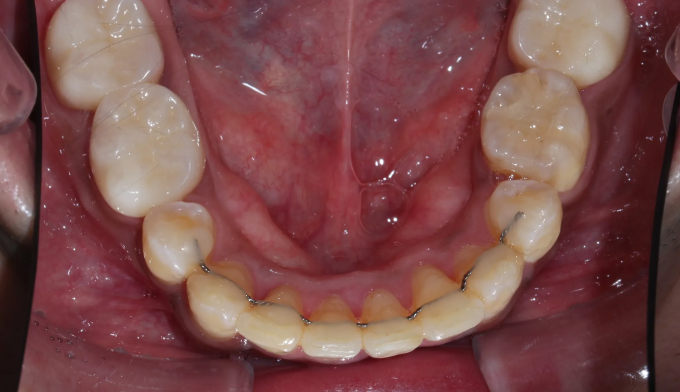

뻐드러진 앞니로 인한 돌출입과, 구강위생관리 부족으로 인한 다수의 충치가 관찰된 케이스입니다.

교정시작 전 충치가 많은 분들은 교정치료과정에서 더 많은 충치가 생길 가능성이 매우 높기 때문에 먼저 양치질교육을 비롯한 전반적인 구강위생교육이 이루어져야 합니다. 그리고 급한 충치를 먼저 치료하고 교정치료에 들어갑니다.

충치가 진행된 부분이 워낙 광범위하고 많아, 무리해서 치아를 전부 치료하지 않았습니다. 최소한으로 치료하고 지켜보기로 하였습니다.

교정치료는 24개월 소요되었으며, 뻐드러진 앞니로 인해 다물기 어려웠던 입술도 이제는 편하게 다물 수 있게 되었습니다.